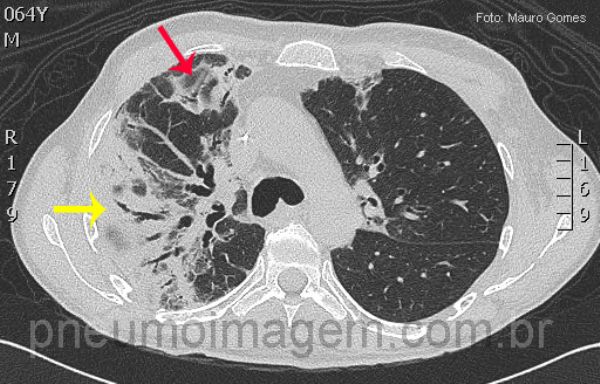

Neste corte, consolidação no lobo superior direito com broncogramas aéreos no seu interior (seta amarela). Opacidades em vidro fosco (seta vermelha).

Consolidation in the right upper lobe with air bronchograms inside (yellow arrow). Ground-glass opacities (red arrow). In Invasive Aspergillosis can occur nodules (with or without cavitation), consolidations, peribronchovascular opacities and masses.